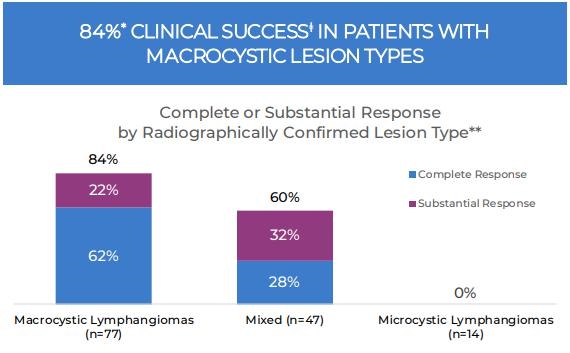

Overall, 310 subjects were enrolled with intent to treat: 246 subjects were randomized to the immediate (ITG, N=171) and delayed (DTG, N=75) treatment groups; 64 subjects were nonrandomized and assigned to the open-label group. Analysis of the primary efficacy endpoint (N=150) demonstrated clinical success (complete and/or substantial response) in 69% of patients in the ITG 6 months after enrollment, while 7.5% of patients in the DTG experienced spontaneous regression of a LM during this time interval (p < 0.0001)). When the results were analyzed by lesion type across all treatment groups, a successful outcome was observed in 84% and 60% of patients with macrocystic and mixed-cystic LM, respectively. None of the patients with microcystic LM demonstrated clinical success with OK-432 therapy. The results of the retrospective analysis were consistent with the results observed in the original analysis (Smith et al. 2009).

Figure 2: patients with radiographically confirmed macrocystic lesions had the greatest likelihood of clinical success and in those patients with mixed lesions, clinical success was also present.

| ǂ | Clinical Success was defined as complete or substantial response. |

| * | Reflects data prior to dosing with OK-432. After dosing, the clinical success rate was 66%, which was not statistically different from the ITG. |

| ** | Results were analyzed by lesion type across all treatment groups. |